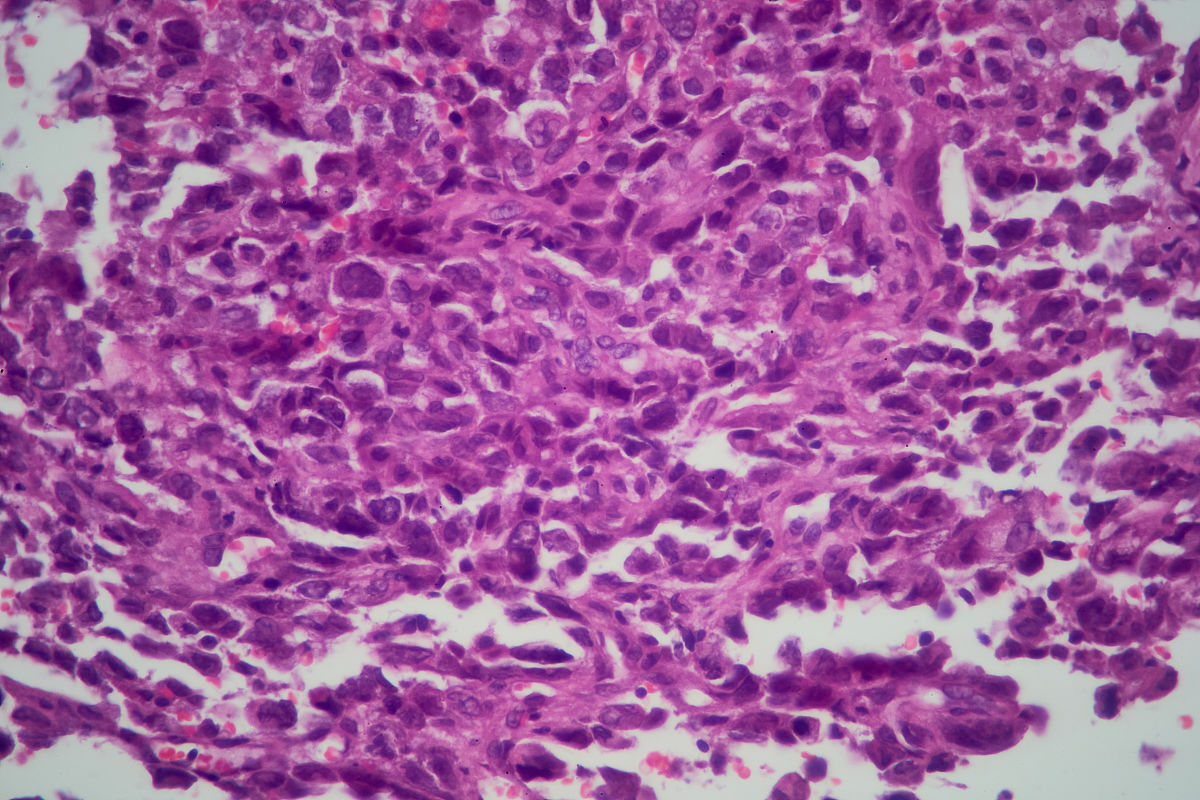

根据提供的信息,复查结果显示肺组织中存在低分化腺癌浸润,并且部分癌细胞发生了退变。这个结论可以解读为低分化腺癌在肺组织中有复发或进展的迹象。

部分癌细胞发生退变可能指的是这些癌细胞发生了一些形态或结构上的改变,可能与治疗或其他因素有关。这种情况下,可能有一部分癌细胞变得不像原始的低分化腺癌细胞,而是呈现出更不成熟或更异常的特征。

曾经被诊断为低分化腺癌并接受过治疗。低分化腺癌复查结论为:肺组织中见低分化癌浸润部分细胞伴退变。怎么解读这个结论属于复发吗?部分癌细胞发生了退变属于什么情况?是好还是不好?